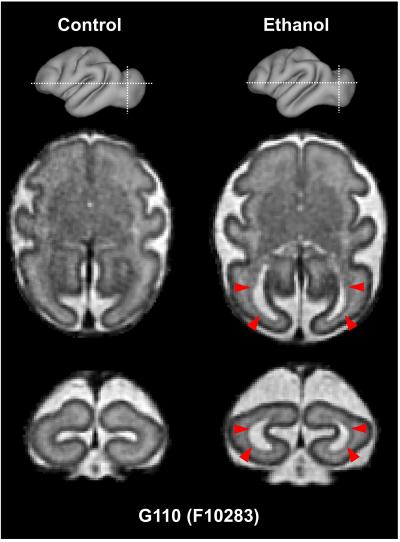

A study in monkeys finds that exposure to alcohol early in gestation affects the development of brain regions involved in motor control. Early intervention for infants suffering from fetal alcohol syndrome can reduce long-term cognitive and behavioral impacts. Recent advances in motion correction have improved the quality and resolution of 3D MRI of the fetal brain. Using in utero MRI, Xiaojie Wang and colleagues found that exposure to alcohol in the first trimester affects the development of brain regions involved in motor control in rhesus macaques. The authors examined a group of 28 female macaques. Fourteen of the macaques consumed 1.5 g of alcohol per kilogram of body weight per day. At three time-points during gestation, the authors used in utero MRI to image the fetal brains, immediately followed by electrophysiological assays of brain activity. Total brain volumes of ethanol-exposed and control fetuses did not differ. In the human equivalent of the third trimester, however, both the cerebellum and brain stem regions in the ethanol-exposed fetuses were smaller, and motor-related white matter maturation was altered, compared with controls. Electrophysiological recordings suggested that the differences are functionally significant. According to the authors, noninvasive in utero MRI may be sufficiently sensitive to be developed as a diagnostic tool for fetal alcohol syndrome as early as the third trimester.

ARTICLE #19-19048: "In utero MRI identifies consequences of early-gestation alcohol drinking on fetal brain development in rhesus macaques," by Xiaojie Wang et al.